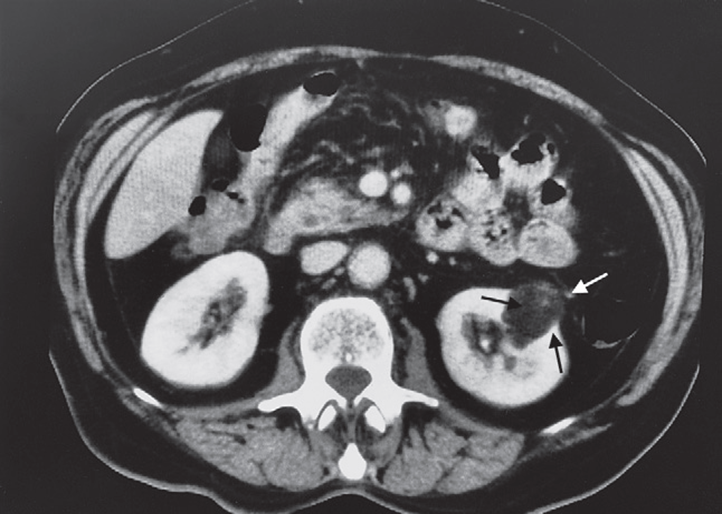

Abdominal CT

Tumor with macroscopic fat deposits -No calcification It has a strong association with tuberous sclerosis Angiomyolipoma seen as a well-defined mass (arrows) of fat density on CT.